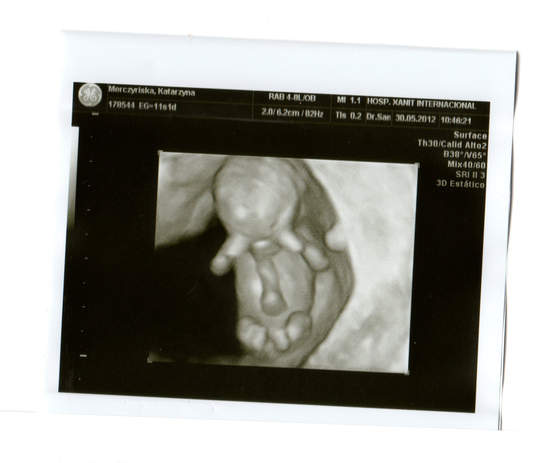

Zrobil mi juz USG genetyczne przez powloki brzuszne i wszystko pieknie widzialam. Z dzidzia wszystko w porzadku. Widzialam juz glowe, raczki, nozki i oczywiscie slyszlam serduszko. Straszie ruchliwy byl bo fikal nogami ze hej. Cudowny widok !!!

Moja dzidzia ma juz 4,5 cm. I wyglada na to ze wszystko jest w najlepszym porzadku.

Wrzucam zdjecia...